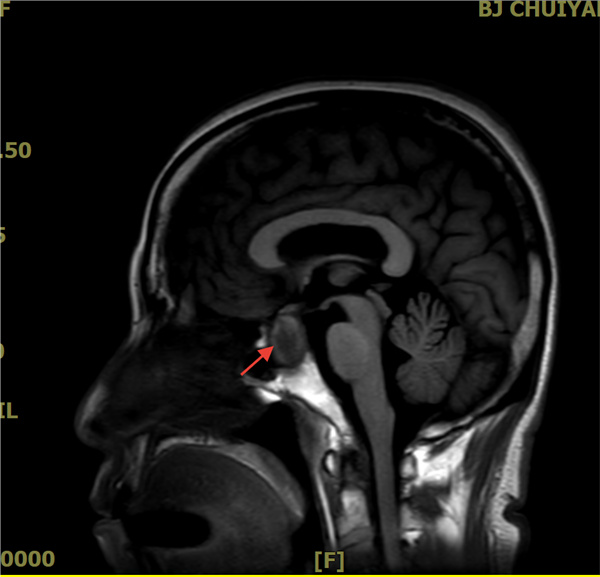

近日,清华大学附属垂杨柳医院神经内科收治了这样一位患者,该患者因“头晕、头痛一周”就诊,随后出现视物模糊、走路不稳、看东西重影等症状。初步怀疑为后循环缺血,但经过头颅核磁等详细检查,并未发现明显动静脉血管问题,却意外发现一个“垂体大腺瘤”。综合判断,正是这个垂体瘤引起了患者的上述症状。今天,我们就来一起了解下垂体瘤的相关知识。

鞍区MRI平扫+增强:诊断的“金标准”,清晰显示肿瘤大小、位置及与周围结构关系。